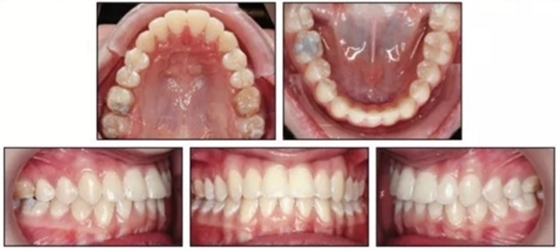

患者繼續(xù)佩戴活動(dòng)保持器,治療后13月隨訪提示其仍處于一個(gè)穩(wěn)定的咬合關(guān)系。(圖5)